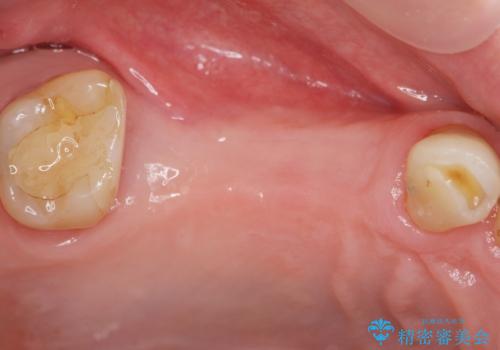

- 右上の奥歯を失ってしまい、「全然モノが噛めない、しっかりと噛めるようになりたい。」

、と入れ歯ではなくインプラント治療を希望され来院されました。

3本の歯が失われた状態を、2本のインプラントで支えるブリッジでの咬合機能回復を計画します。